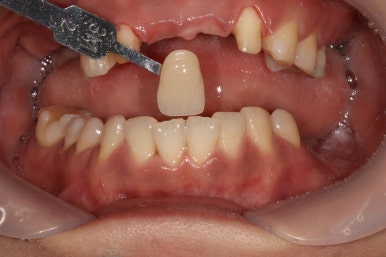

왼쪽위 처음 내원하셨을 당시, 오른쪽이 앞니 지르코니아 완성 후 정면 사진입니다.

보시면 파란색 화살표로 표시된 두 측절치에 기존에 치료받으셨던 PFM 브릿지의 경계가 드러나 회색 라인이 생기신 것을 보실 수 있고, 잇몸이 올라가버려 비교적 비 심미적인 모습인 것을 확인하실 수 있습니다.

지르코니아 브릿지로 교체함으로써 예쁜 첫인상을 완성해드렸어요.

이렇게 치료 중간에 환자분과 상의하면서 치아 색상을 적절히 채득해놓기에 가능한 일입니다.

본 환자분 같은 경우에는 자연스러운 치아 색상을 원하셔서 따뜻한 느낌의 색상으로 완성하였는데, 경우에 따라 보다 밝은 색상으로의 변화도 가능합니다! 연예인 라미네이트처럼요.